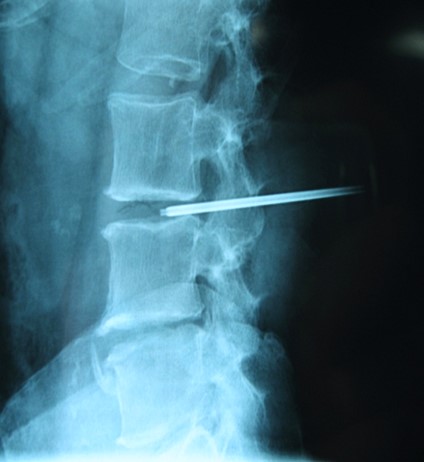

Vertbroplastika primenom stenta

View the embedded image gallery online at:

https://www.klinikaelit.com/minimalno-invazivne-porcedure#sigProId7e0694e114